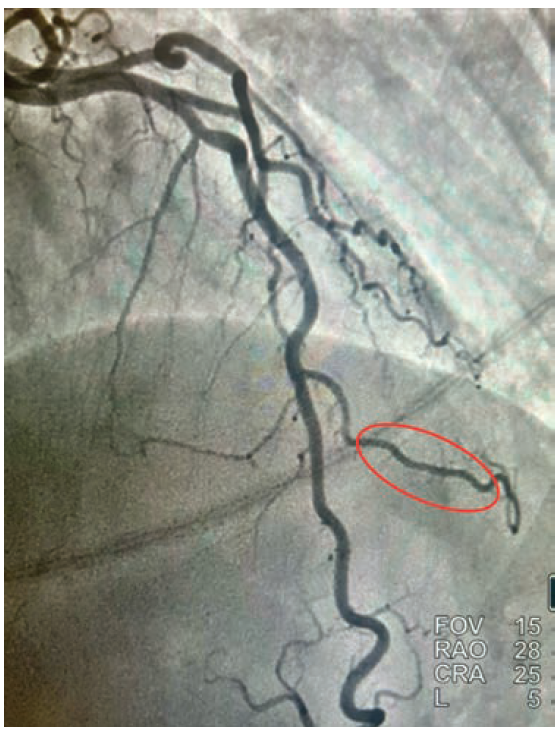

• Cardiac catheterization: Catheterization revealed normal coronary arteries with severe systolic compression of the second diagonal branch (Figures 1-2; Video).

Given the fact that the patient continued to have recurrent episodes of ventricular tachycardia, along with elevated troponin, and an echocardiogram showing reduced LVEF with slightly more pronounced hypokinesis of the septal and apical walls, the decision was made to rule out ischemia as a possible cause. She subsequently underwent coronary angiography via right radial approach, which revealed a right-dominant system and normal coronary arteries, with the exception of the 2nd diagonal branch of the LAD, which had severe systolic compression, resulting in near-obliteration of the artery with each cardiac cycle (Video).